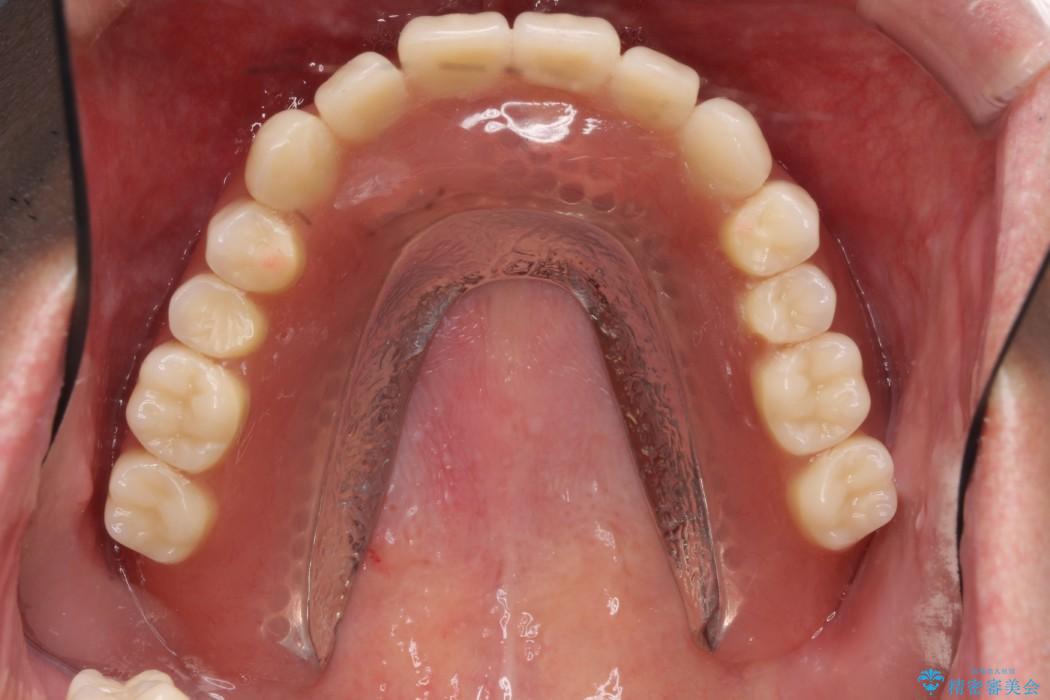

本症例では失った歯を補うため、マグネットを使用したインプラントの入れ歯(マグネットオーバーデンチャー)という維持機構を使用しました。

マグネットタイプは無理な側方力がかかると入れ歯が外れるため、口腔内に設置する装置が他の維持装置と比べてインプラント体や支台歯へ大きな負担がかかることを防止してくれます。

また着脱が簡単であり、磁石の固定によりガタつかず非常に安定します。